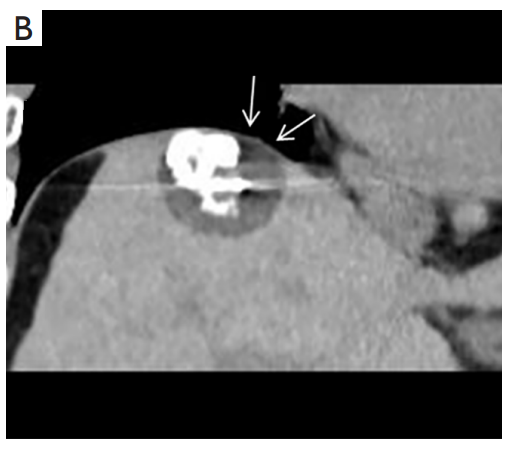

背景:由于一些原因,位于膈肌附近的腫瘤的熱消融在技術(shù)上具有挑戰(zhàn)性。首先,術(shù)中計(jì)算機(jī)掃描和超聲檢查無法清晰顯示射頻消融/微波消融切緣。第二,消融過程中不利的針分布和過熱可能導(dǎo)致肝包膜破裂,并對膈、肺和心臟造成嚴(yán)重?fù)p傷。第三,即使使用人工腹水,仍有9~22%的患者因肝周粘連或腫瘤位置靠近肝表面而導(dǎo)致膈肌熱損傷。冷凍消融可能是毗鄰膈肌的HCC的一種有前途的治療方法,因?yàn)樵谙谶^程中使用CT和US可以很好地顯示腫瘤邊緣。盡管一些研究評(píng)估了在高危區(qū)域使用冷凍消融治療HCC,但很少有研究針對膈肌臨近區(qū)域。

背景:肝癌是中國最常見的惡性腫瘤之一,發(fā)病率和死亡率都很高。雖然手術(shù)切除是最好的治療方法,但大多數(shù)患者處于晚期或直到住院才有手術(shù)指征。對于單個(gè)腫瘤直徑小于5厘米的患者,微創(chuàng)治療與手術(shù)切除效果相當(dāng);多個(gè)病灶小于3個(gè),單個(gè)病灶最大直徑小于3cm;不侵犯血管、膽管、鄰近器官和遠(yuǎn)處轉(zhuǎn)移。雖然一些傳統(tǒng)消融技術(shù)方式可以使部分患者受益,但不適用于特殊部位肝癌(定義為毗鄰大血管、肝外臟器和重要結(jié)構(gòu)的腫瘤)的治療。冷凍消融作為一種相對較新的治療方式,具有明顯的冰球效果、療效好、激活抗腫瘤免疫、并發(fā)癥發(fā)生率低等優(yōu)點(diǎn),尤其適用于特殊部位肝癌患者的治療。我們的研究目的是探討CA治療特殊部位肝癌的安全性、可行性和有效性。